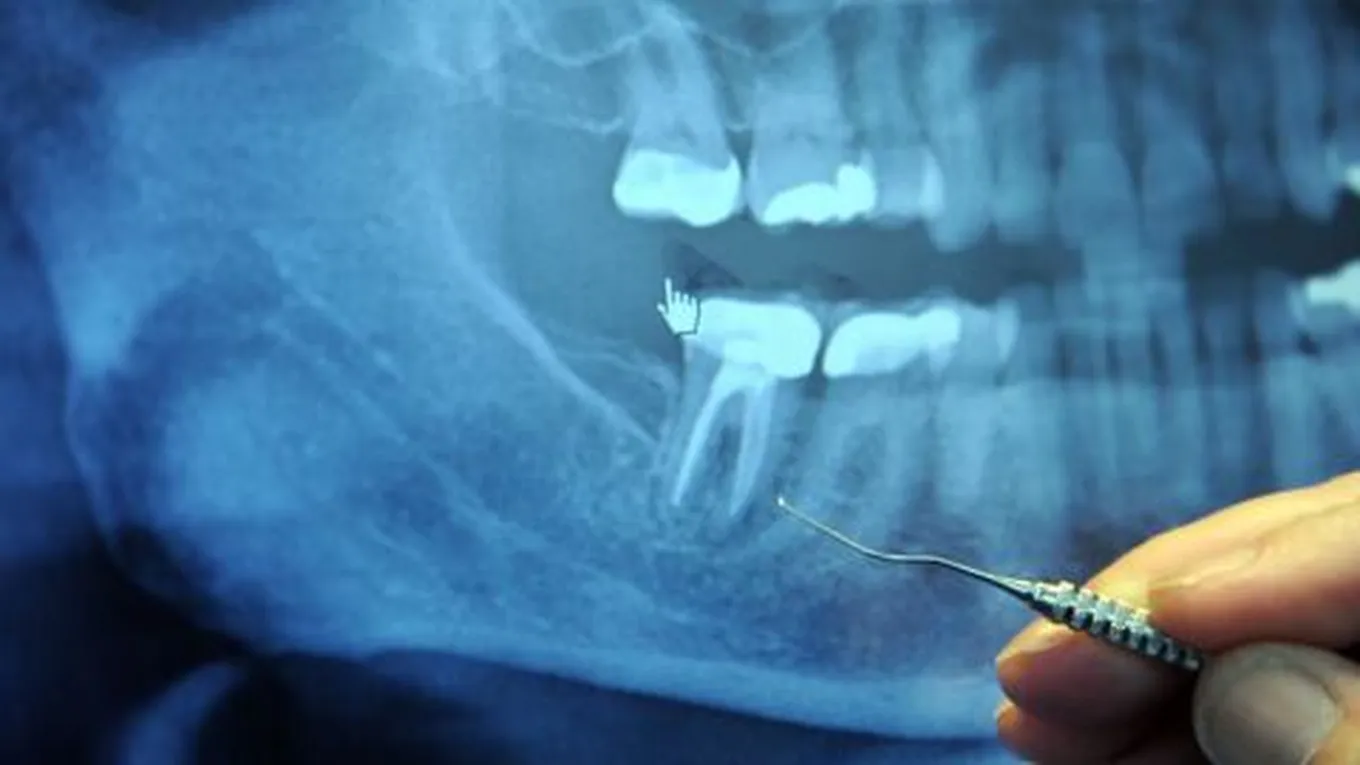

جاءت تسمية ضرس العقل بهذا الاسم ، كونه آخر الاسنان الطبيعية التي تجدها في الفم ، إضافة لظهوره غالباً بفترة نضج الإنسان العقلي ، وذلك ما بين عمر 18 إلى 25 عام . كما وتجد أربعة منه اثنان في الفك السفلي ، واثنان في الفك العلوي . وضرس العقل بدوره يبقى أكثر الأسنان المتعرّضة لعدم بزوغها ، وانطمارها ، كما وقد تكون غير ظاهرة أبداً في بعض الأحيان.

وذلك يرجع لكونها في أغلب الأحيان لا تجد لها مكاناً يتسع لظهورها ، ممّا يؤدي كما ذكرنا مسبقاً لعدم بزوغها أو انطمارها ، أو عدم ظهورها ، ونضيف إلى ذلك إمكانية ظهور جزء منها في الفم ، مع بقاء الجزء المتبقي منها مدفون في عظام الفك تحديداً .

وفي بعض الحالات يفضّل طبيب الأسنان خلع ضرس العقل من باب الوقاية ، نظرا لرؤيته بأن ضرس العقل في حالته هذه قد يؤدي لإصابة الشخص بالتهابات وآلام هو بغنى عنها . وغالباً ما تتم عملية خلع ضرس العقل في المستشفى ، ويُنصح الشخص قبل خضوعه للعملية باتباع ارشادات ونصائح معيّنة كعدم شربه أو أكله لأي شيء في منتصف ليل اليوم الذي يسبق يوم العملية .